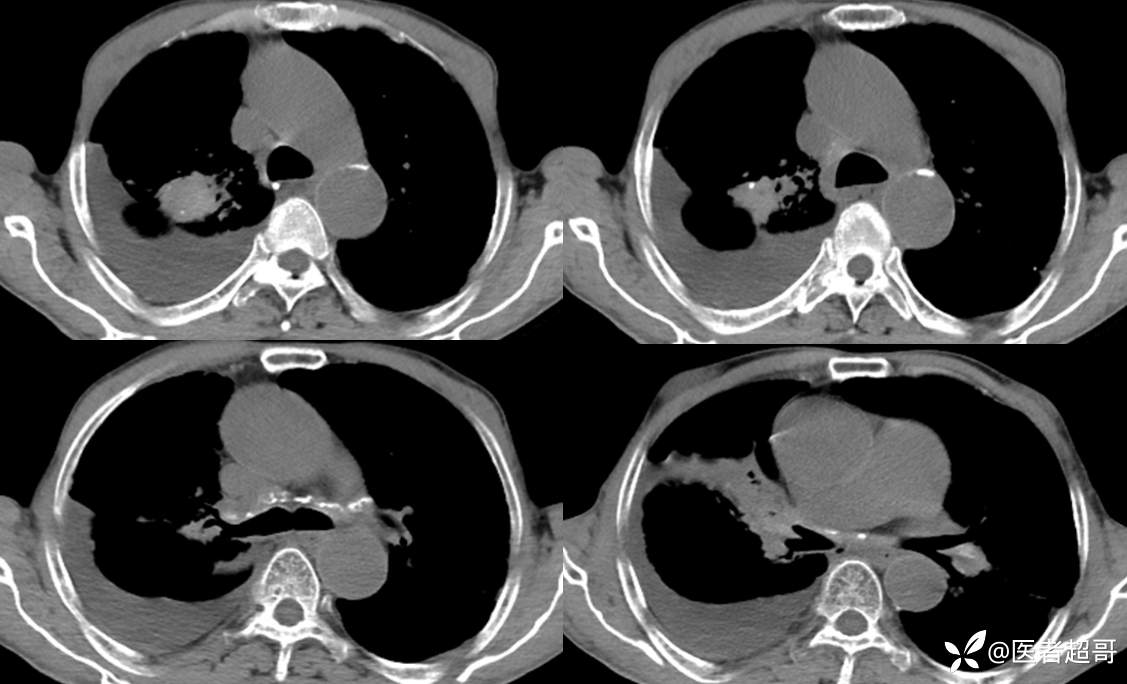

患者,男,72岁,农民,于2021年05月26日17时20分因"发作性精神行为异常10+天"入院。@丁香影像频道